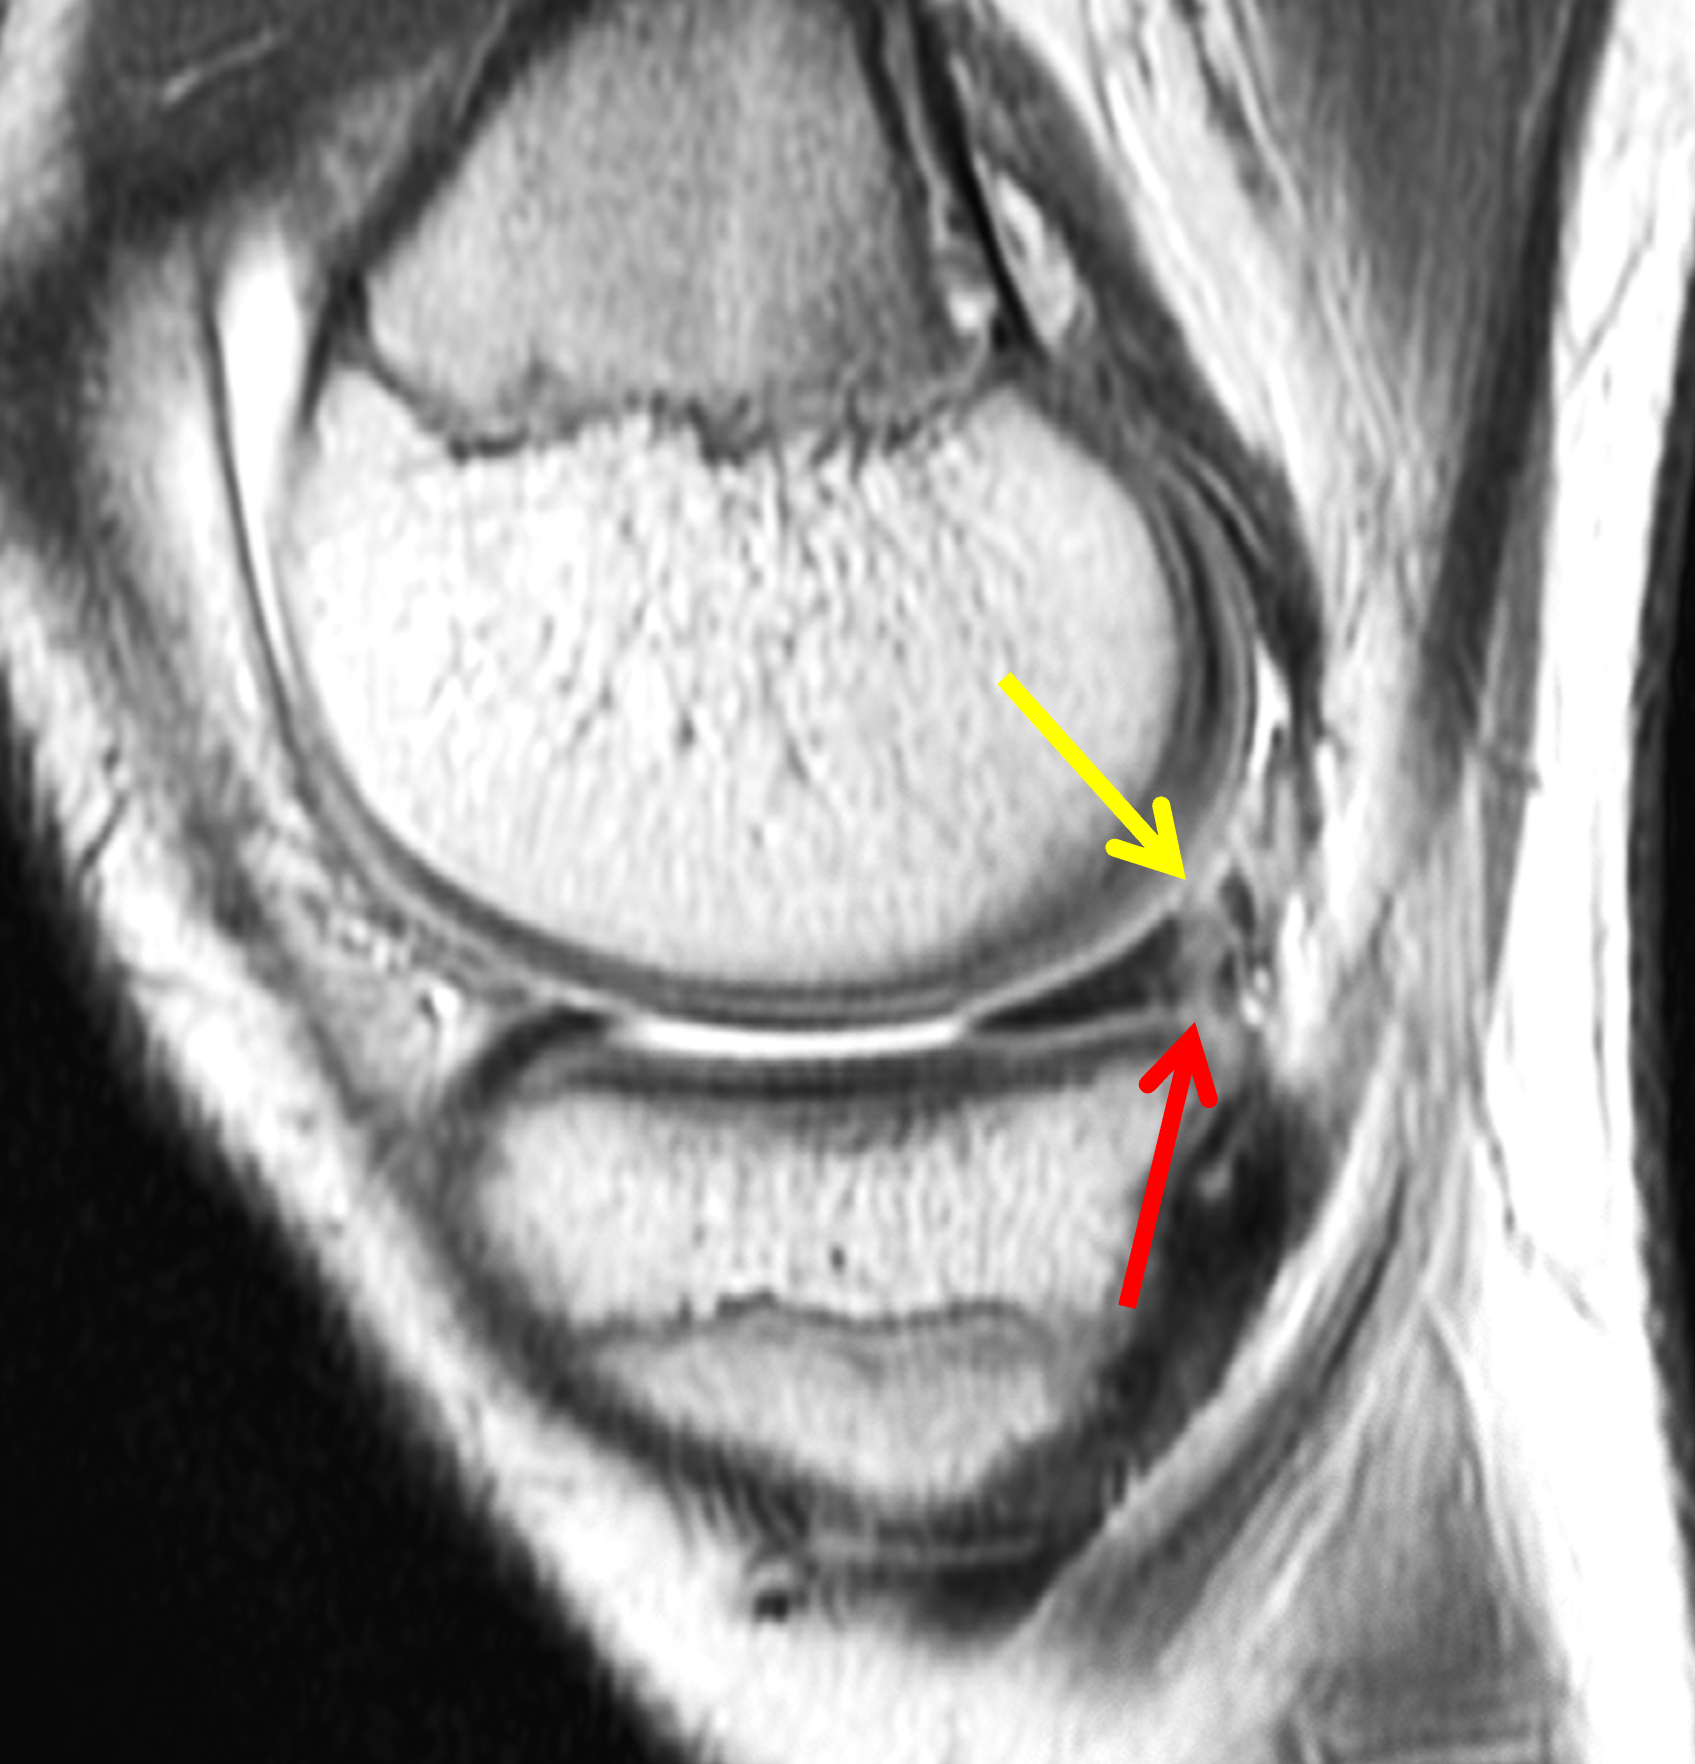

A 19-year-old collegiate baseball player sustained a twisting injury to the knee 3 weeks earlier. Sagittal (1A) proton density-weighted fat-suppressed image through the intercondylar notch, (1B and 1C) proton density-weighted images through the medial compartment, and (1D) fat-suppressed proton density image through the medial compartment are provided. What are the findings? What is your diagnosis?

Figure 2: (2A) Sagittal image through the intercondylar notch shows a complete tear of the anterior cruciate ligament (arrowheads). (2B and 2C) Near the posterior meniscocapsular junction of the medial meniscus, there is disruption of the posterior meniscotibial ligament (red arrow) and irregularity of the posterior meniscocapsular ligament (yellow arrow). (2D) On the fluid-sensitive sequence, linear high signal intensity is interposed between the ligaments and the posterior horn of the medial meniscus (arrowheads).

Anterior cruciate ligament tear with a medial meniscal ramp lesion.